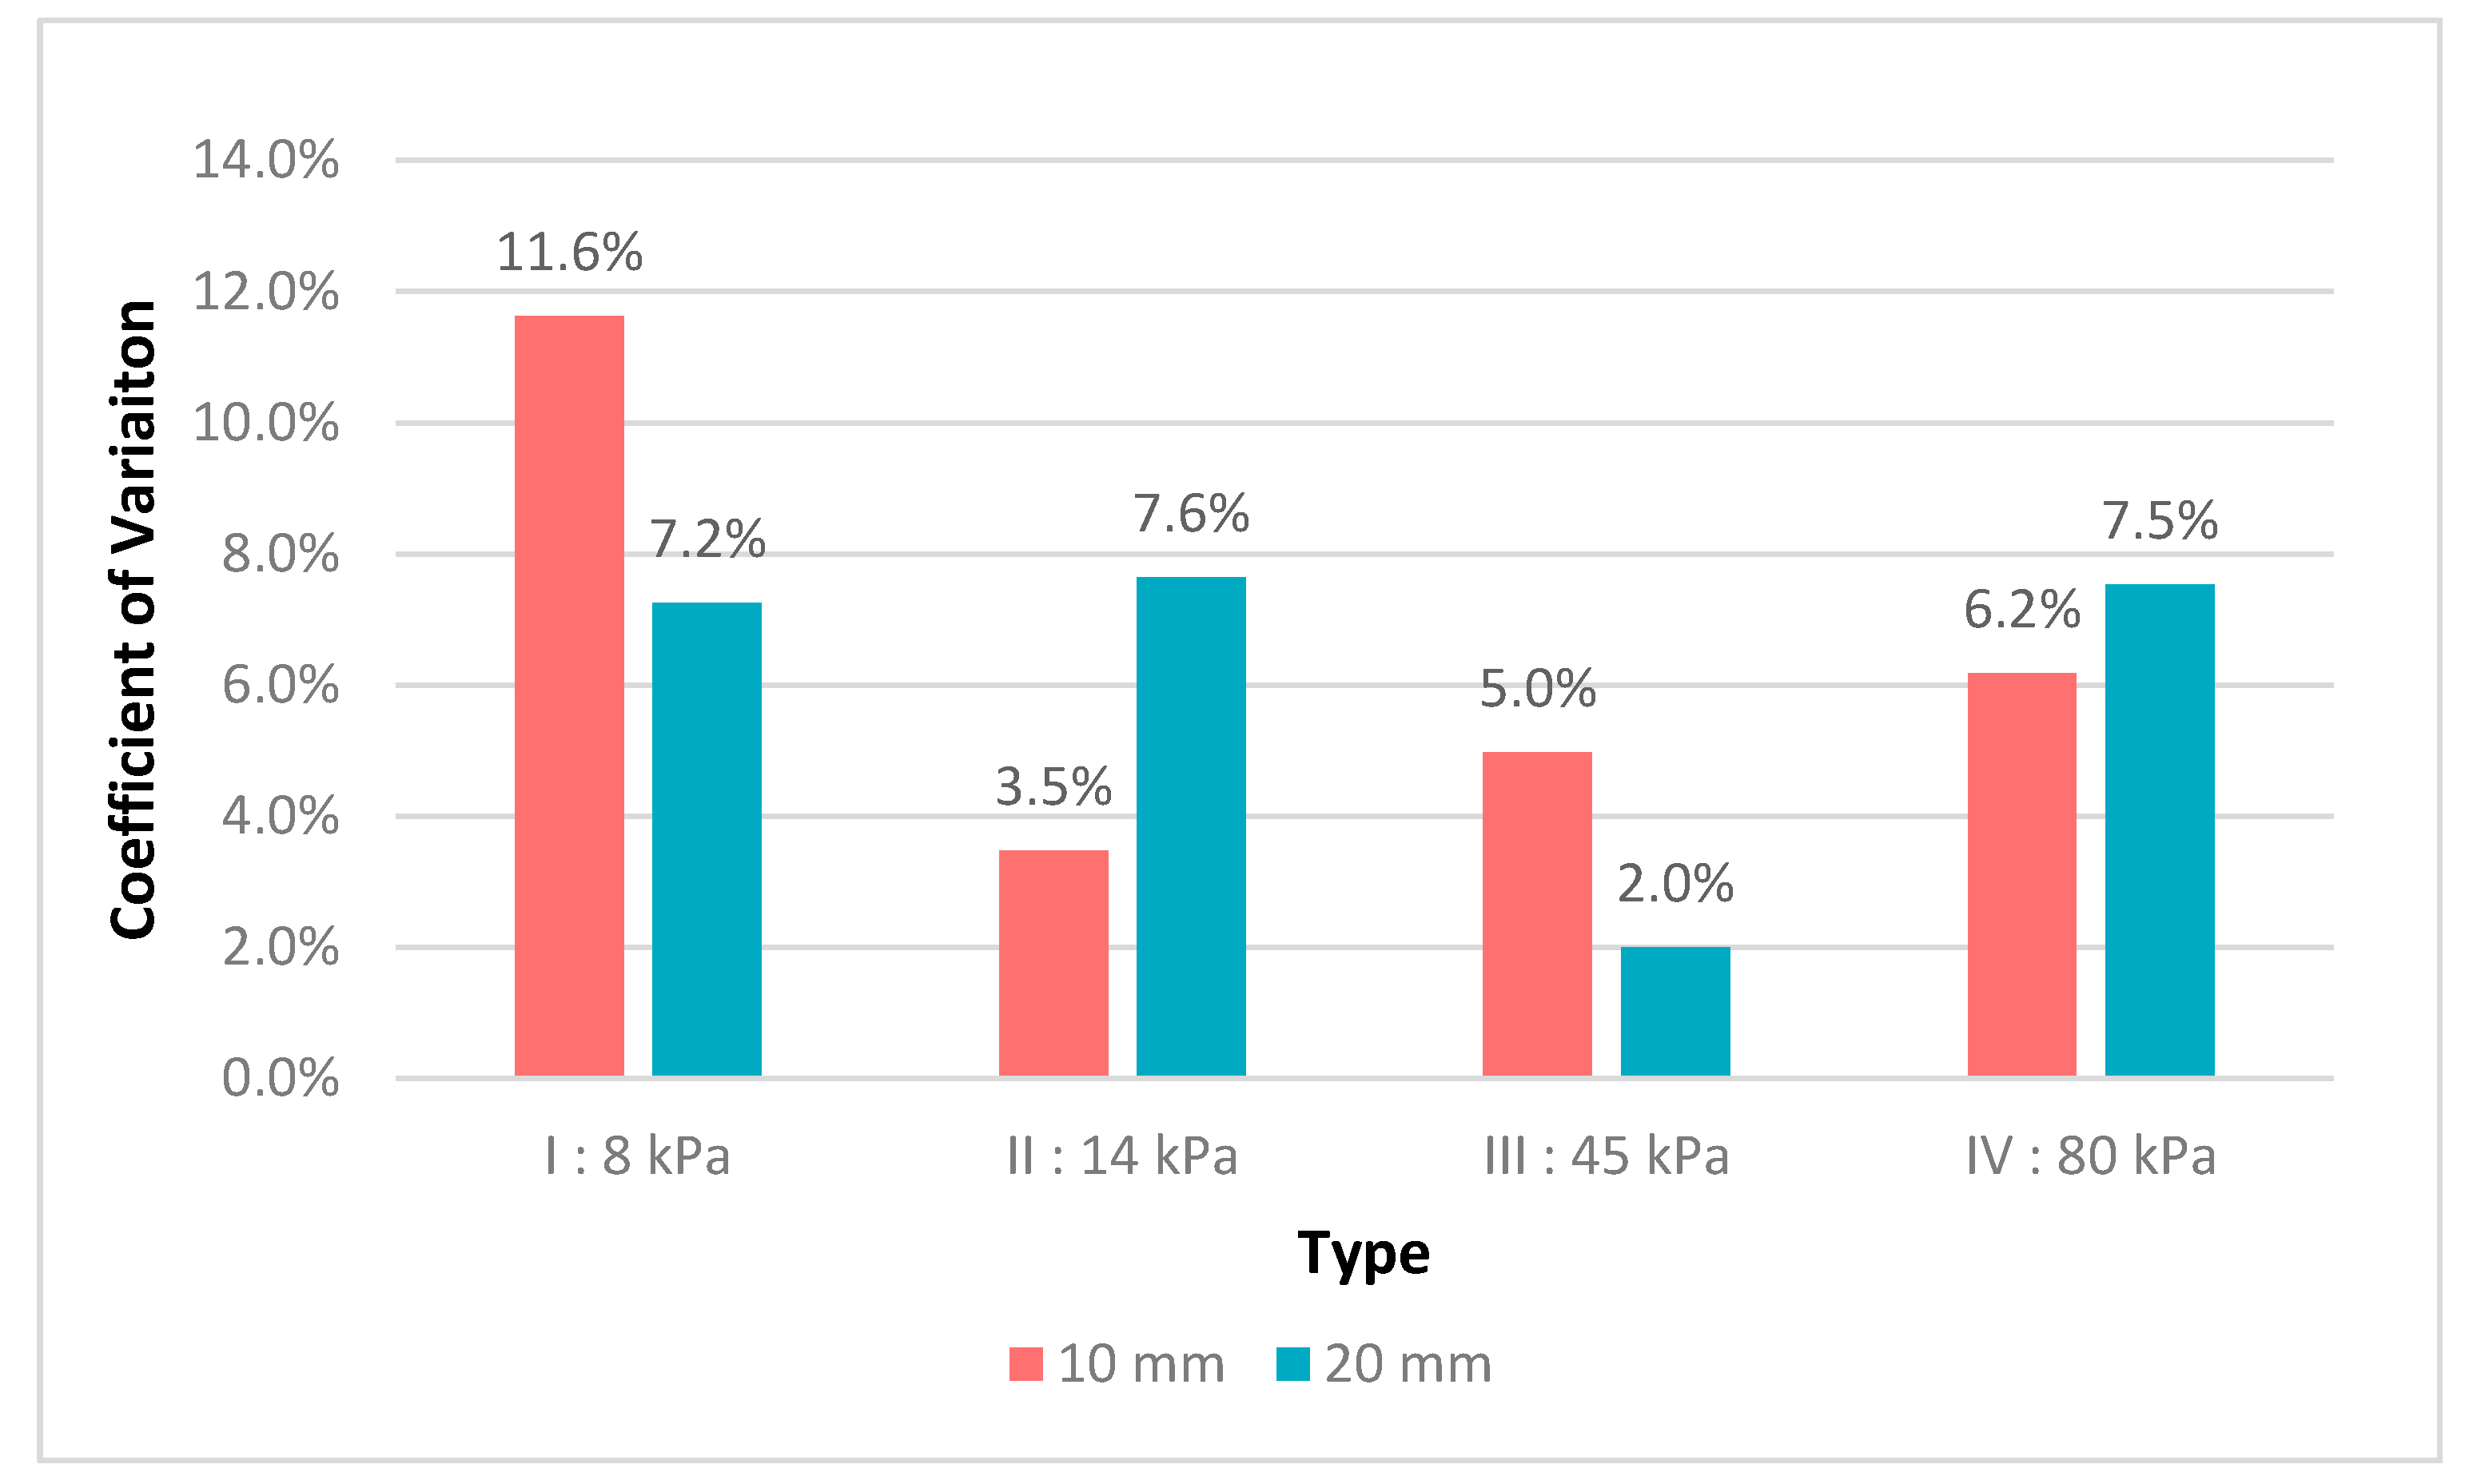

3.1. Robustness Evaluation Regarding Size and Type of Inclusions